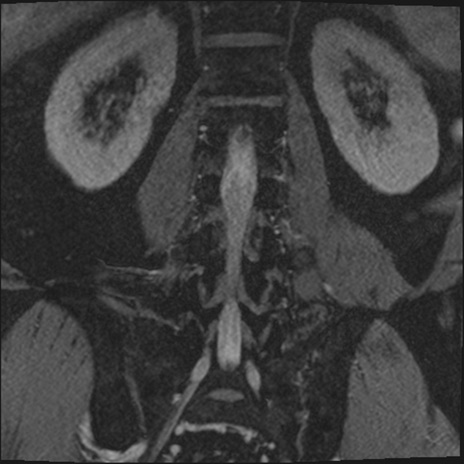

【整形】TIPS症例2 腰椎MRI 3D(冠状断像)

【症例】70歳代男性

【主訴】左下肢痛

【現病歴】2週間前くらいから腰痛、左下肢痛あり。左臀部から大腿、下腿外側のしびれが常時ある。歩行とともに同部位の痛みあり。

【身体所見】Lasegue70-/60+、Bragard-/±、PTR ±/±、ATR -/-、IP 5/5、TA 5/4、TS 5/5、EHL 右第1足趾なし/3、FHL 5/5、hypersthesia(-)、足背動脈触知良好

異常所見と診断は?